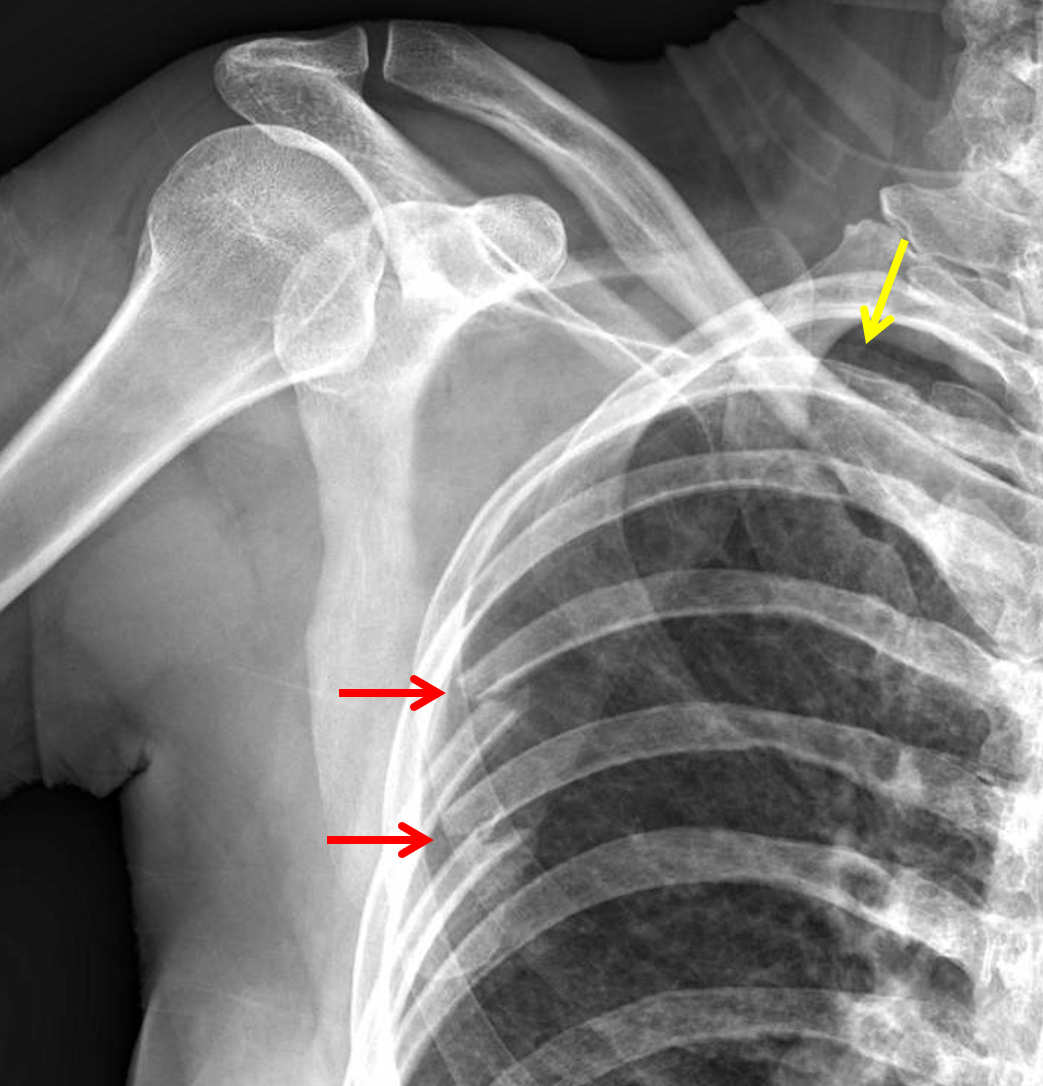

from atlas.mudr.org

Radiology case Rib fracture, lung contusion, hematoma, pneumothorax

Serial rib fracture Pneumothorax Comminuted fracture of scapula Rib Fracture And Pneumothorax Traumatic rib fractures are the consequence of significant forces impacting the chest wall and are most commonly due to blunt. Rib fractures can also lead to a collapsed lung (sometimes called pneumothorax). Simple pneumothorax converts to a tension pneumothorax if the lung defect acts as a one way valve, which allows ongoing air leak into pleural space without. Learn about. Rib Fracture And Pneumothorax.